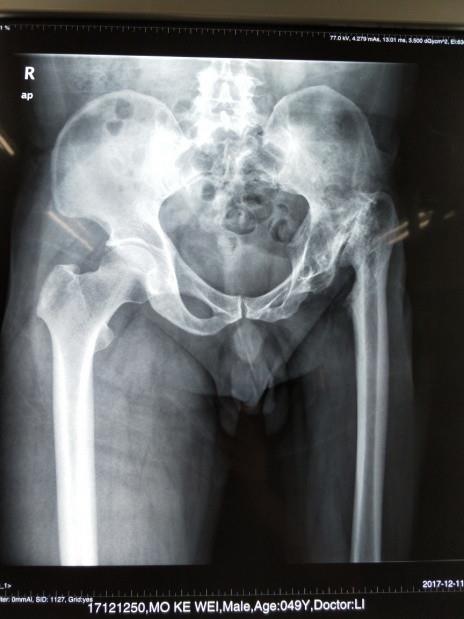

开展数字化技术,3D打印技术

开展数字化技术,3D打印技术在骨科诊疗中的应用,提高骨科诊疗水平,获得广西科技厅重大专项建设项目。

开展人工髋、膝关节置换手术